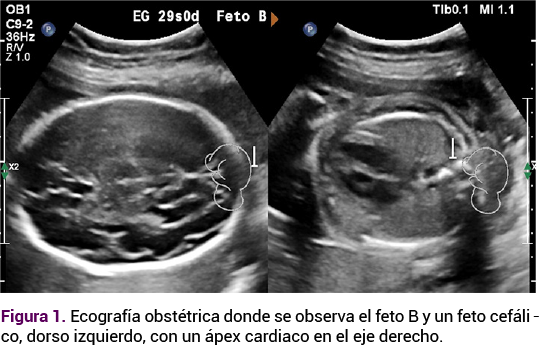

Los estudios postnatales del neonato con diagnóstico prenatal de situs inversus incluyeron una ecografía transfontanelar normal, así como una radiografía de tórax (Figura 2) y ecografía de abdomen, que confirmaron los hallazgos descritos, sin otras alteraciones, también se obtuvo el cariotipo neonatal que descartó alteraciones numéricas o estructurales en los cromosomas.

<strong>Figura 2</strong>

Figura 2.